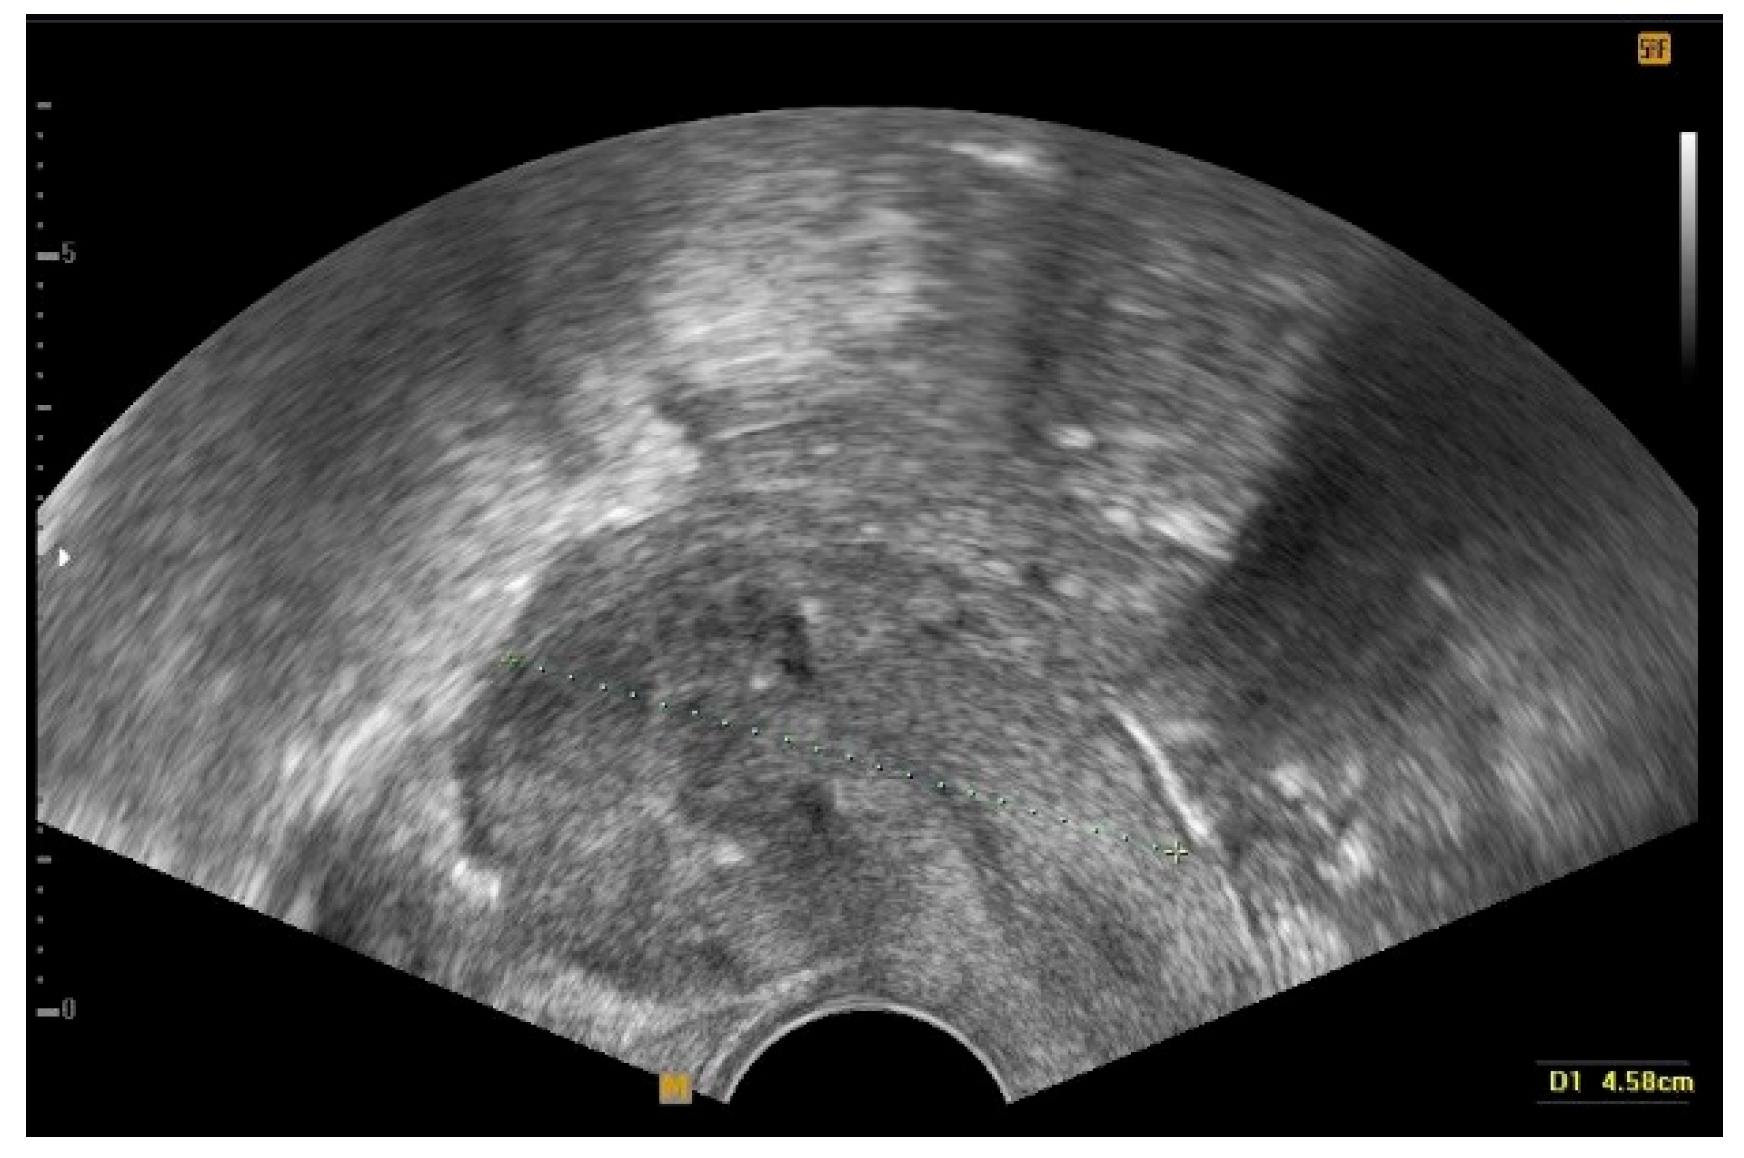

Clinical Outcomes of Conservative Surgery for Diffuse Uterine Leiomyomatosis: Preliminary Experience of 17 Cases in a Single Center

2. Materials and Methods